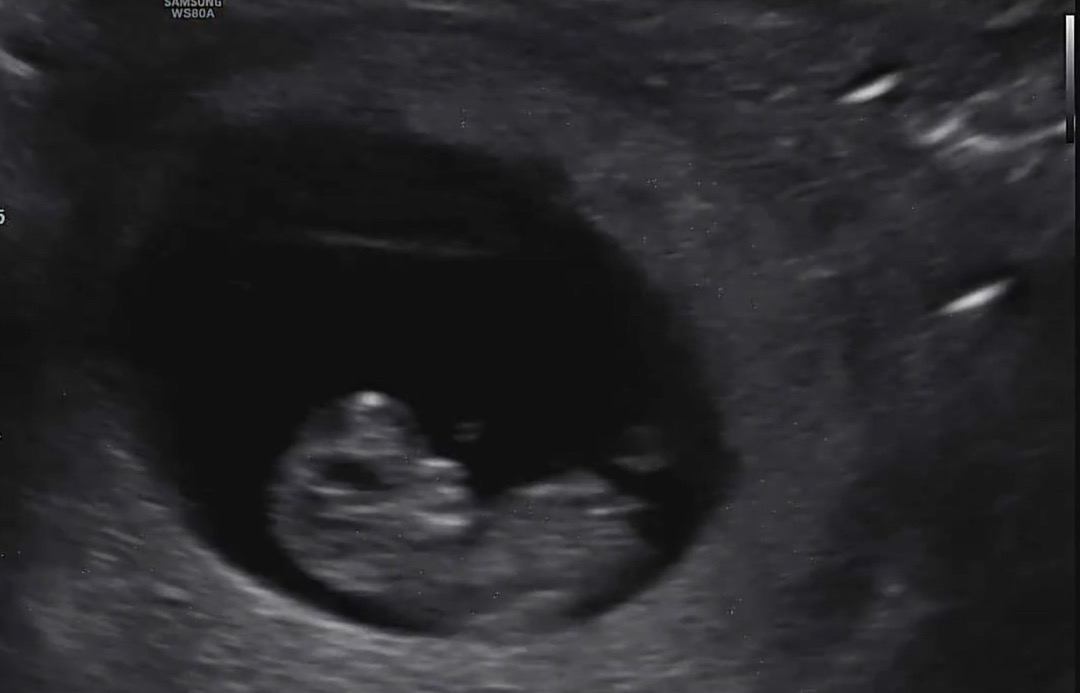

10주 3일인데 오늘 젤리곰 보고 왔어요 ㅎㅎ 복부초음파라 선명하진 않은데 각도법 너무 신기하더라구요!